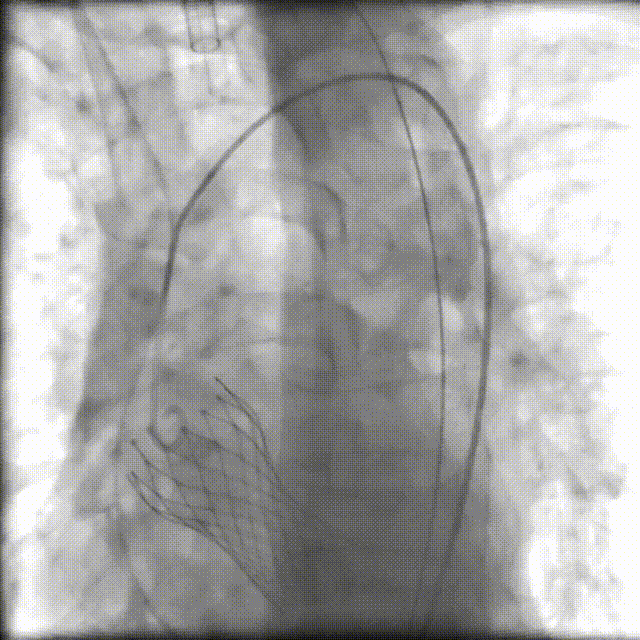

术中,我院心血管内科、手术麻醉科、介入医学科、超声医学科、ICU、呼吸与危重症医学科、胸心血管外科、输血科等医护专家组成“护心团队”,在四川大学华西医院心血管内科魏家富教授团队的指导和护航下,经股动脉入路建立工作路径,成功置入新的人工主动脉瓣(VenusA-Plus瓣膜)。术后造影及超声提示未见明显反流,无瓣周漏,瓣膜置入位置良好,形态完整,术后跨瓣压差及舒张压即刻改善,未出现相关并发症,手术圆满成功。目前,患者已顺利出院!

术后造影

入路造影